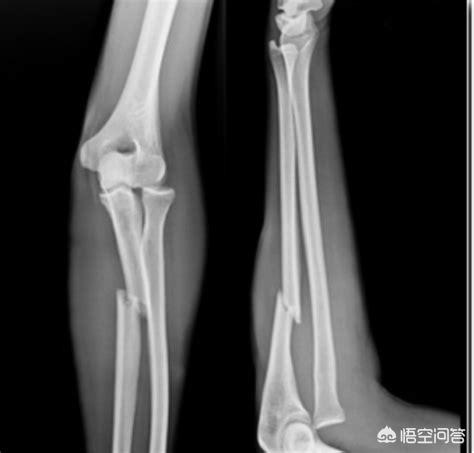

Comme nous l'avons mentionné dans une précédente question-réponse, les radiographies, les tomographies et les IRM sont généralement disponibles pour aider les médecins à diagnostiquer les patients souffrant d'une hernie discale. Les radiographies sont relativement peu coûteuses et constituent un bon test de dépistage de la maladie ; elles sont également généralement requises dans le dossier médical des patients hospitalisés. Lors d'une consultation orthopédique ambulatoire, votre chirurgien orthopédique demandera généralement une radiographie pour examiner l'état général des os, tandis que pour des maladies spécifiques, le chirurgien pourra demander des tests plus spécifiques à l'état du patient. Bien entendu, ces examens sont plus coûteux que les radiographies !

Mais parfois, un prix plus élevé ne signifie pas nécessairement une image plus claire. Dans le cas d'une fracture, une radiographie est beaucoup plus claire qu'une IRM, et le choix de l'examen dépend de la situation spécifique du patient ! Regardez le film radiographique suivant, vous verrez qu'il s'agit d'une fracture !